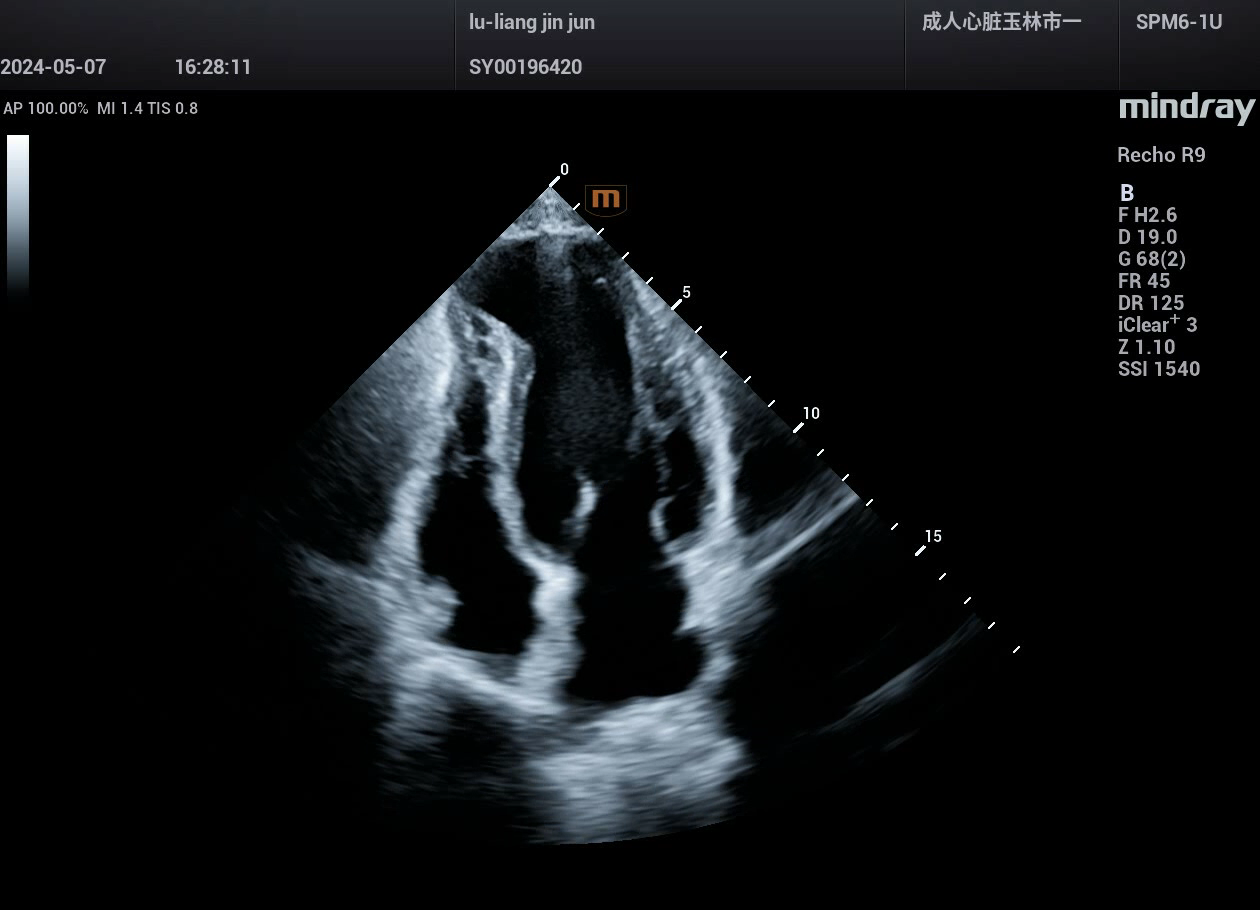

病例,风湿性心脏瓣膜病(风心病),迈瑞心脏彩超鲲鹏Recho R9,2024年5月

来源玉林市第一人民医院超声科,迈瑞超声鲲鹏实现超声事业高质量发展